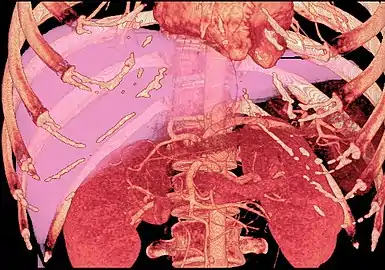

Couinaud classification system

Shape of human liver in animation, with eight Couinaud segments labelled

In the widely used Couinaud system, the functional lobes are further divided into a total of eight subsegments based on a transverse plane through the bifurcation of the main portal vein.[28] The caudate lobe is a separate structure that receives blood flow from both the right- and left-sided vascular branches.[29][30] The Couinaud classification divides the liver into eight functionally independent liver segments. Each segment has its own vascular inflow, outflow and biliary drainage. In the centre of each segment are branches of the portal vein, hepatic artery, and bile duct. In the periphery of each segment is vascular outflow through the hepatic veins.[31] The classification system uses the vascular supply in the liver to separate the functional units (numbered I to VIII) with unit 1, the caudate lobe, receiving its supply from both the right and the left branches of the portal vein. It contains one or more hepatic veins which drain directly into the inferior vena cava.[28] The remainder of the units (II to VIII) are numbered in a clockwise fashion:[31]

With the recent advances of noninvasive imaging, living liver donors usually have to undergo imaging examinations for liver anatomy to decide if the anatomy is feasible for donation. The evaluation is usually performed by multidetector row computed tomography (MDCT) and magnetic resonance imaging (MRI). MDCT is good in vascular anatomy and volumetry. MRI is used for biliary tree anatomy. Donors with very unusual vascular anatomy, which makes them unsuitable for donation, could be screened out to avoid unnecessary operations.